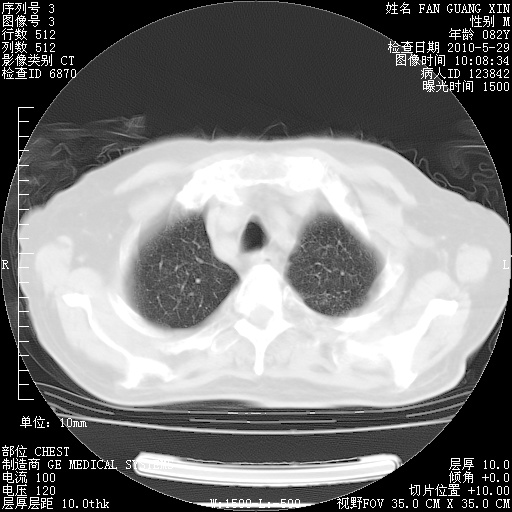

再治疗10天后的肺部CT

再治疗10天后的肺部CT 纵膈窗

从白细胞总数和中性比例看好像合并感染。肺部纹理好像比上次多,支气管炎?其他感染?

阅读此次胸部CT,肺间质渗出性改变较入院时有吸收。目前从体温、白细胞、中性分叶明显增高,肯定存在细菌感染(发生医院感染哦,若无消化道及泌尿系统等感染的依据,肺部感染可能大)。若你院头孢哌酮舒巴坦钠耐药率较高,同意你的方案,若48小时体温仍高,可考虑使用碳青霉稀类抗菌药物,同时可予超声雾化、注意滴数时加大液体量。白蛋白33.30g/L较低哦,需加强营养等支持治疗。